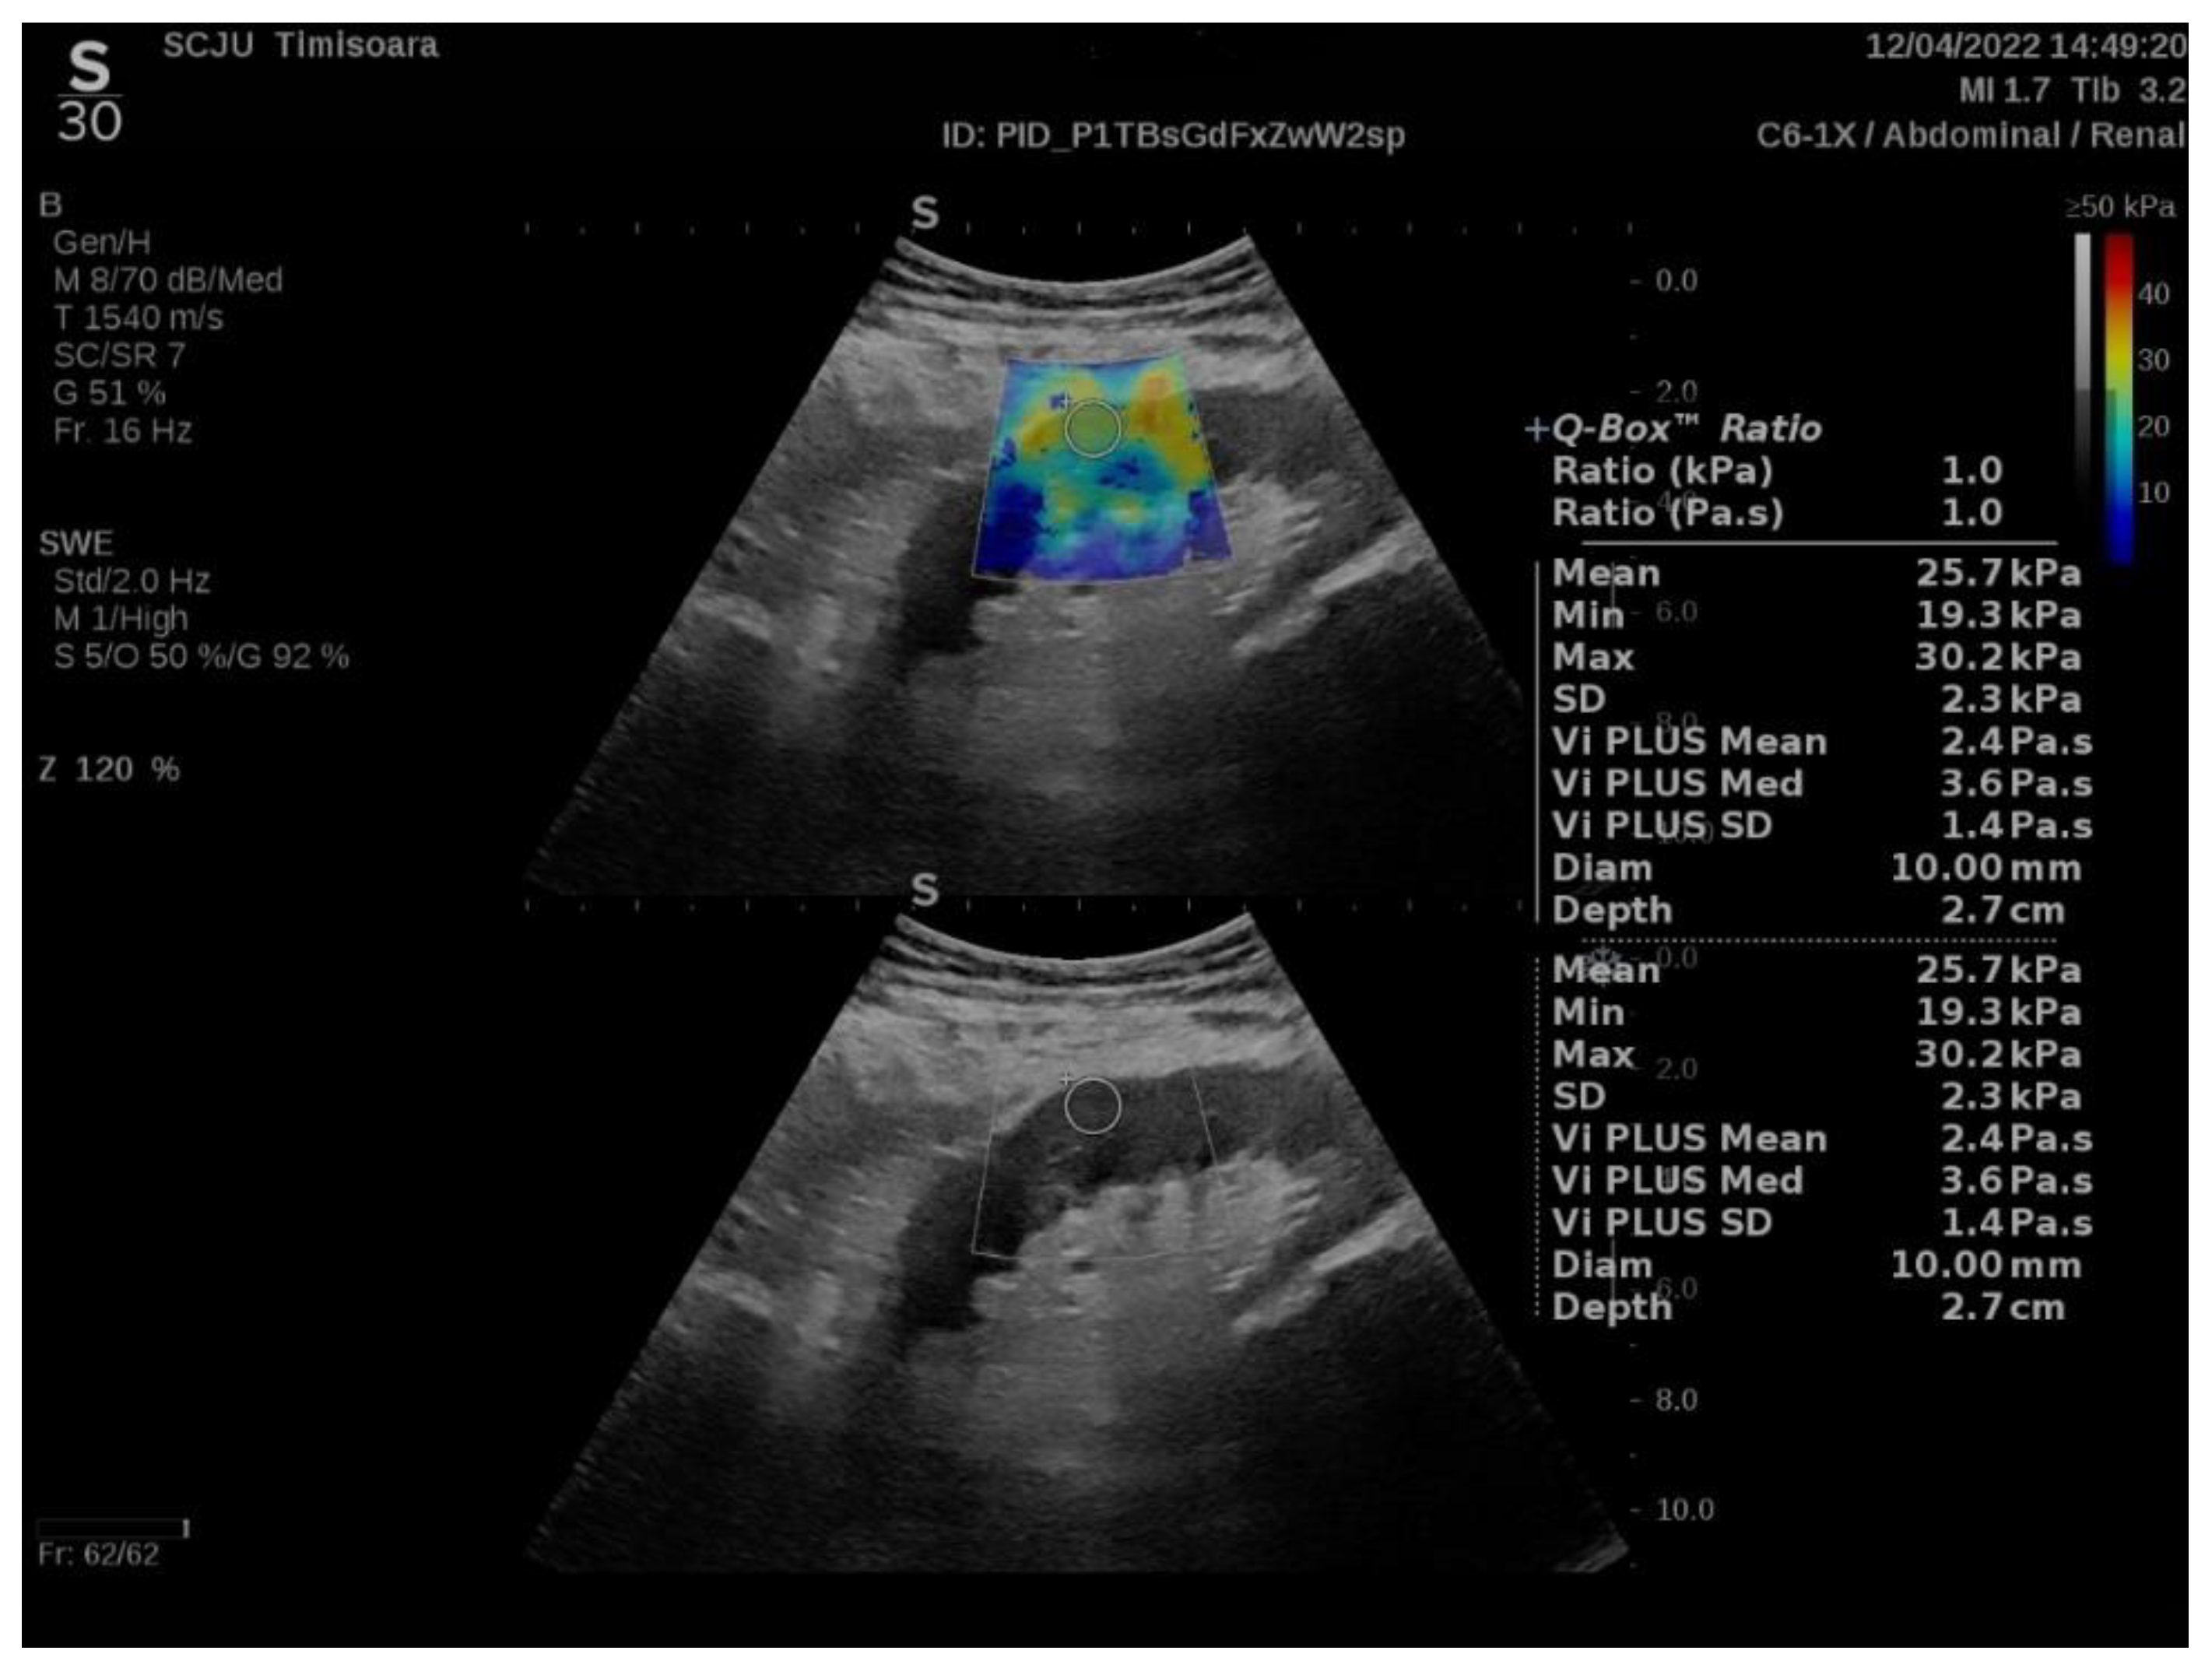

Measurements were performed for the middle portion of the renal graft, in the subcapsular cortex, with the patient in dorsal decubitus immediately after emptying the bladder. For each measurement (with ROI set by the renal software system at 10 mm displayed as a Q-box on the screen), the software of the apparatus provided the following information: the mean value of YM—the weighted arithmetic mean of all values in the ROI (displayed as Mean); the minimum value of the YM in the ROI (displayed as Min on the screen); the maximum value of YM in the ROI (displayed as Max on the screen); the standard deviation of the YM values in the ROI (displayed as SD); the sum of all Vi PLUS values in the ROI divided by the number of values (displayed as Vi PLUS Mean); the median values of Vi PLUS (displayed as Vi PLUS Med); the standard deviation of the Vi PLUS values in the ROI (displayed as Vi PLUS SD); the distance between the skin and the examined cortical region (=kidney depth, displayed as Depth in cm); and the diameter of the ROI (displayed as Diam in mm) (Figure 1).

Figure 1.

Quantitative elasticity map of the middle portion subcapsular cortex of a transplanted kidney.